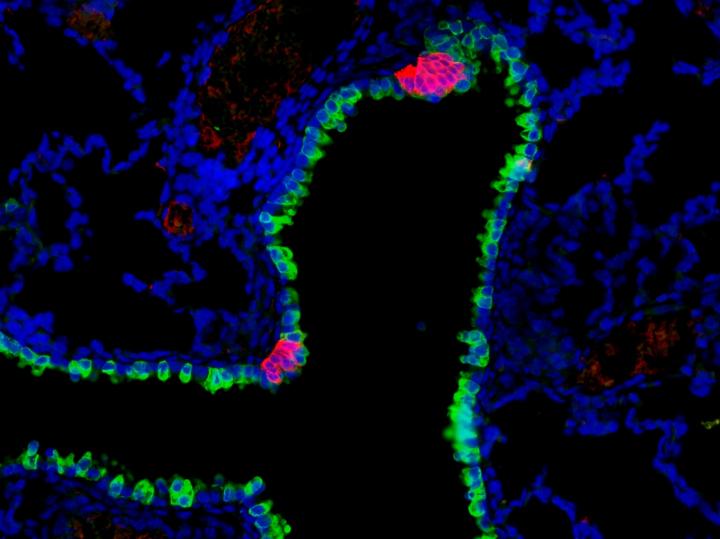

MADISON, Wis. - An uncommon and little-studied type of cell in the lungs has been found to act like a sensor, linking the pulmonary and central nervous systems to regulate immune response in reaction to environmental cues.

The cells, known as pulmonary neuroendocrine cells or PNECs, are implicated in a wide range of human lung diseases, including asthma, pulmonary hypertension, cystic fibrosis and sudden infant death syndrome, among others.

"These cells make up less than one percent of the cells in the airway epithelium," the layer of cells that lines the respiratory tract, explains Sun. "Our conclusion is that they are capable of receiving, interpreting and responding to environmental stimuli such as allergens or chemicals mixed with the air we breathe."

The Wisconsin group homed in on a pair of genes known as ROBO1 and ROBO2. Mutations in the genes had previously been implicated in CDH. By knocking out ROBO genes in mice, Sun and her colleagues were able to mimic CDH. Unexpectedly, they also discovered that PNECs were disorganized in the ROBO mutants. In a healthy mouse, PNECs mostly form clusters of cells. "In the mutant, they don't cluster," says Sun. "They stay as solitary cells, and as single cells they are much more sensitive to the environment."

PNECs are the only known cells in the airway lining that are linked to the nervous system. It seems, explains Sun, that they are basically distributed sensors, gathering information from the air and relaying it to the brain. Interestingly, the same cells also receive processed signals back from the brain to amp up their secretion of neuropeptides, which are small protein molecules that are potent regulators of the immune response.